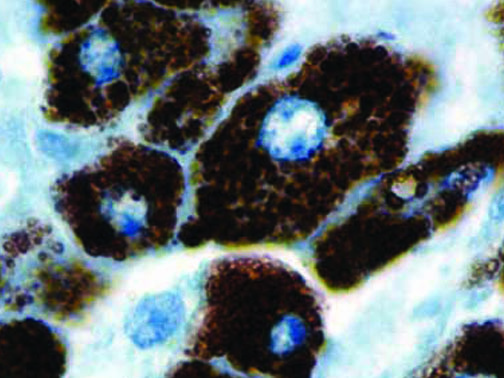

It is the ICU physician who is most likely to witness one of the deadliest manifestations of the abnormal immunological response, the cytokine storm syndrome (CSS). This response is also referred to by some as the cytokine release syndrome (CRS). CSS is characterized by continuous activation and expansion of macrophage and lymphocyte populations, which secrete large amounts of cytokines, causing the cytokine storm. This massive cytokine release is akin to hemophagocytic lymphohistiocytosis (HLH) disease, a syndrome characterized by initial unchecked and persistent activation of cytotoxic T lymphocytes and NK cells.

Clinical and laboratory manifestations of HLH include fever, enlarged liver and/or spleen, neurologic dysfunction, coagulopathy, liver dysfunction, cytopenias (i.e., low levels of erythrocytes, leukocytes, and/or platelets), hypertriglyceridemia, hyperferritinemia, hemophagocytosis, and eventually diminished NK cell activity as the immune system becomes progressively paralyzed. HLH can be familial (primary HLH) or secondary to another disease process (sHLH), such as rheumatic disease, in which it is referred to as macrophage activation syndrome (MAS, characterized by elevated ferritin).